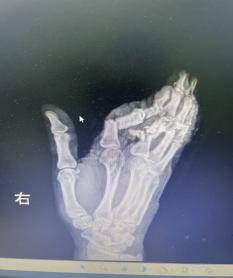

抵达医院时,航医骨外科值班医生已接到通知,在急诊待命。接到余女士的那一刻,值班医生迅速上前为她查看伤情“您别担心,一切有我们”,经快速检查,诊断明确:余女士的右手多指完全离断伤。这是一类极为严重的手部创伤,断指再植手术的黄金时间仅有6-8小时,一旦治疗时间稍有延误,难以保证手指存活。

手术的难度超乎想象:

血管细如发丝:手指的动静脉直径仅0.3-0.8毫米,医生需要在显微镜下用比头发丝还细的缝线进行吻合;

多指同时再植:余女士食指、中指、无名指三指离断,需同时重建血运,给手术医师的精力和体力带来极大考验;

小拇指皮瓣修复:小拇指软组织缺损严重,医生将精心设计皮瓣覆盖创面,避免术后坏死;

骨折内固定+肌腱神经修复:不仅要让手指“活”,更要让手指“能用”。

面对这些困难,许攀峰团队没有却步,沉着应战。他们先是为骨折的手指进行精准内固定,重建骨骼支撑;随后,在显微镜下,一根根寻找断裂的血管、神经和肌腱——清创、修剪、吻合、通血……每一步都如履薄冰,每一次打结都需屏息凝神,手术室内,寂静无声,只有时钟的滴答声在空气中回荡,仿佛在为这场生命的接力默默计时。